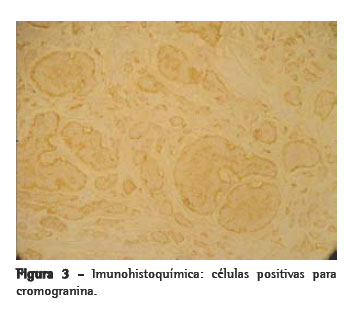

O paciente foi submetido à toracotomia póstero-lateral direita. No intra-operatório, encontramos um tumor de consistência cística e cor amarela, medindo 5,0 × 3,5 × 3,0 cm e pesando 35 g, com áreas de calcificação e localizado no mediastino anterior, sobre a face anterior da veia cava superior, infiltrando o pericárdio e o segmento anterior do lobo superior direito. Iniciou-se dissecção através da abertura da pleura mediastinal, sendo necessárias também ressecção parcial do pericárdio e segmentectomia pulmonar. O mediastino estava livre de linfonodomegalias. O paciente evoluiu sem intercorrências no pós-operatório. Foram encontrados pêlos e secreção sebácea no interior do tumor à abertura da peça (Figura 2). O exame microscópico revelou neoplasia embrionária caracterizada por proliferação de estruturas císticas, ora revestidas por epiderme com glândulas sebáceas e folículos pilosos, ora revestidas por epitélio cilíndrico ciliado de padrão respiratório. Observavam-se feixes musculares lisos, tecido adiposo disposto em lóbulos, agregados linfóides e tecido cartilaginoso. Em certas áreas, havia proliferação de células com núcleos regulares, com cromatina em sal-e-pimenta. Essas células formavam blocos irregulares e apresentavam-se positivas para cromogranina à imunohistoquímica, o que resultou no diagnóstico de teratoma cístico do mediastino com degeneração maligna para tumor carcinóide (Figura 3).

No estudo anatomopatológico da peça, foram encontradas células com núcleos regulares e aspecto em sal-e-pimenta no interior do teratoma. A imunohistoquímica dessa região mostrou-se positiva para cromogranina, o que é característico de tumor carcinóide.(14)